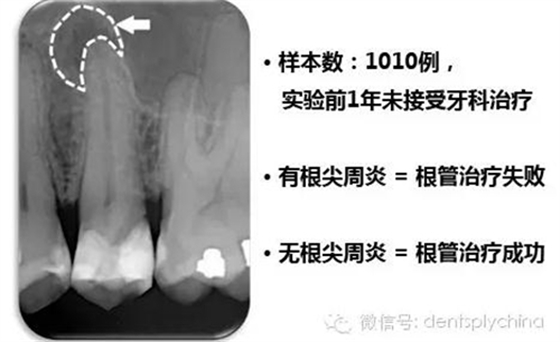

根管治療后牙齒的根尖周狀態(tài)和根管充填和冠部修復的關(guān)系

成功標準: 根尖周健康 = 沒有根尖周炎

作者的結(jié)論

"對于控制根尖周感染而言,冠部修復的質(zhì)量比根管治療的質(zhì)量更重要。"